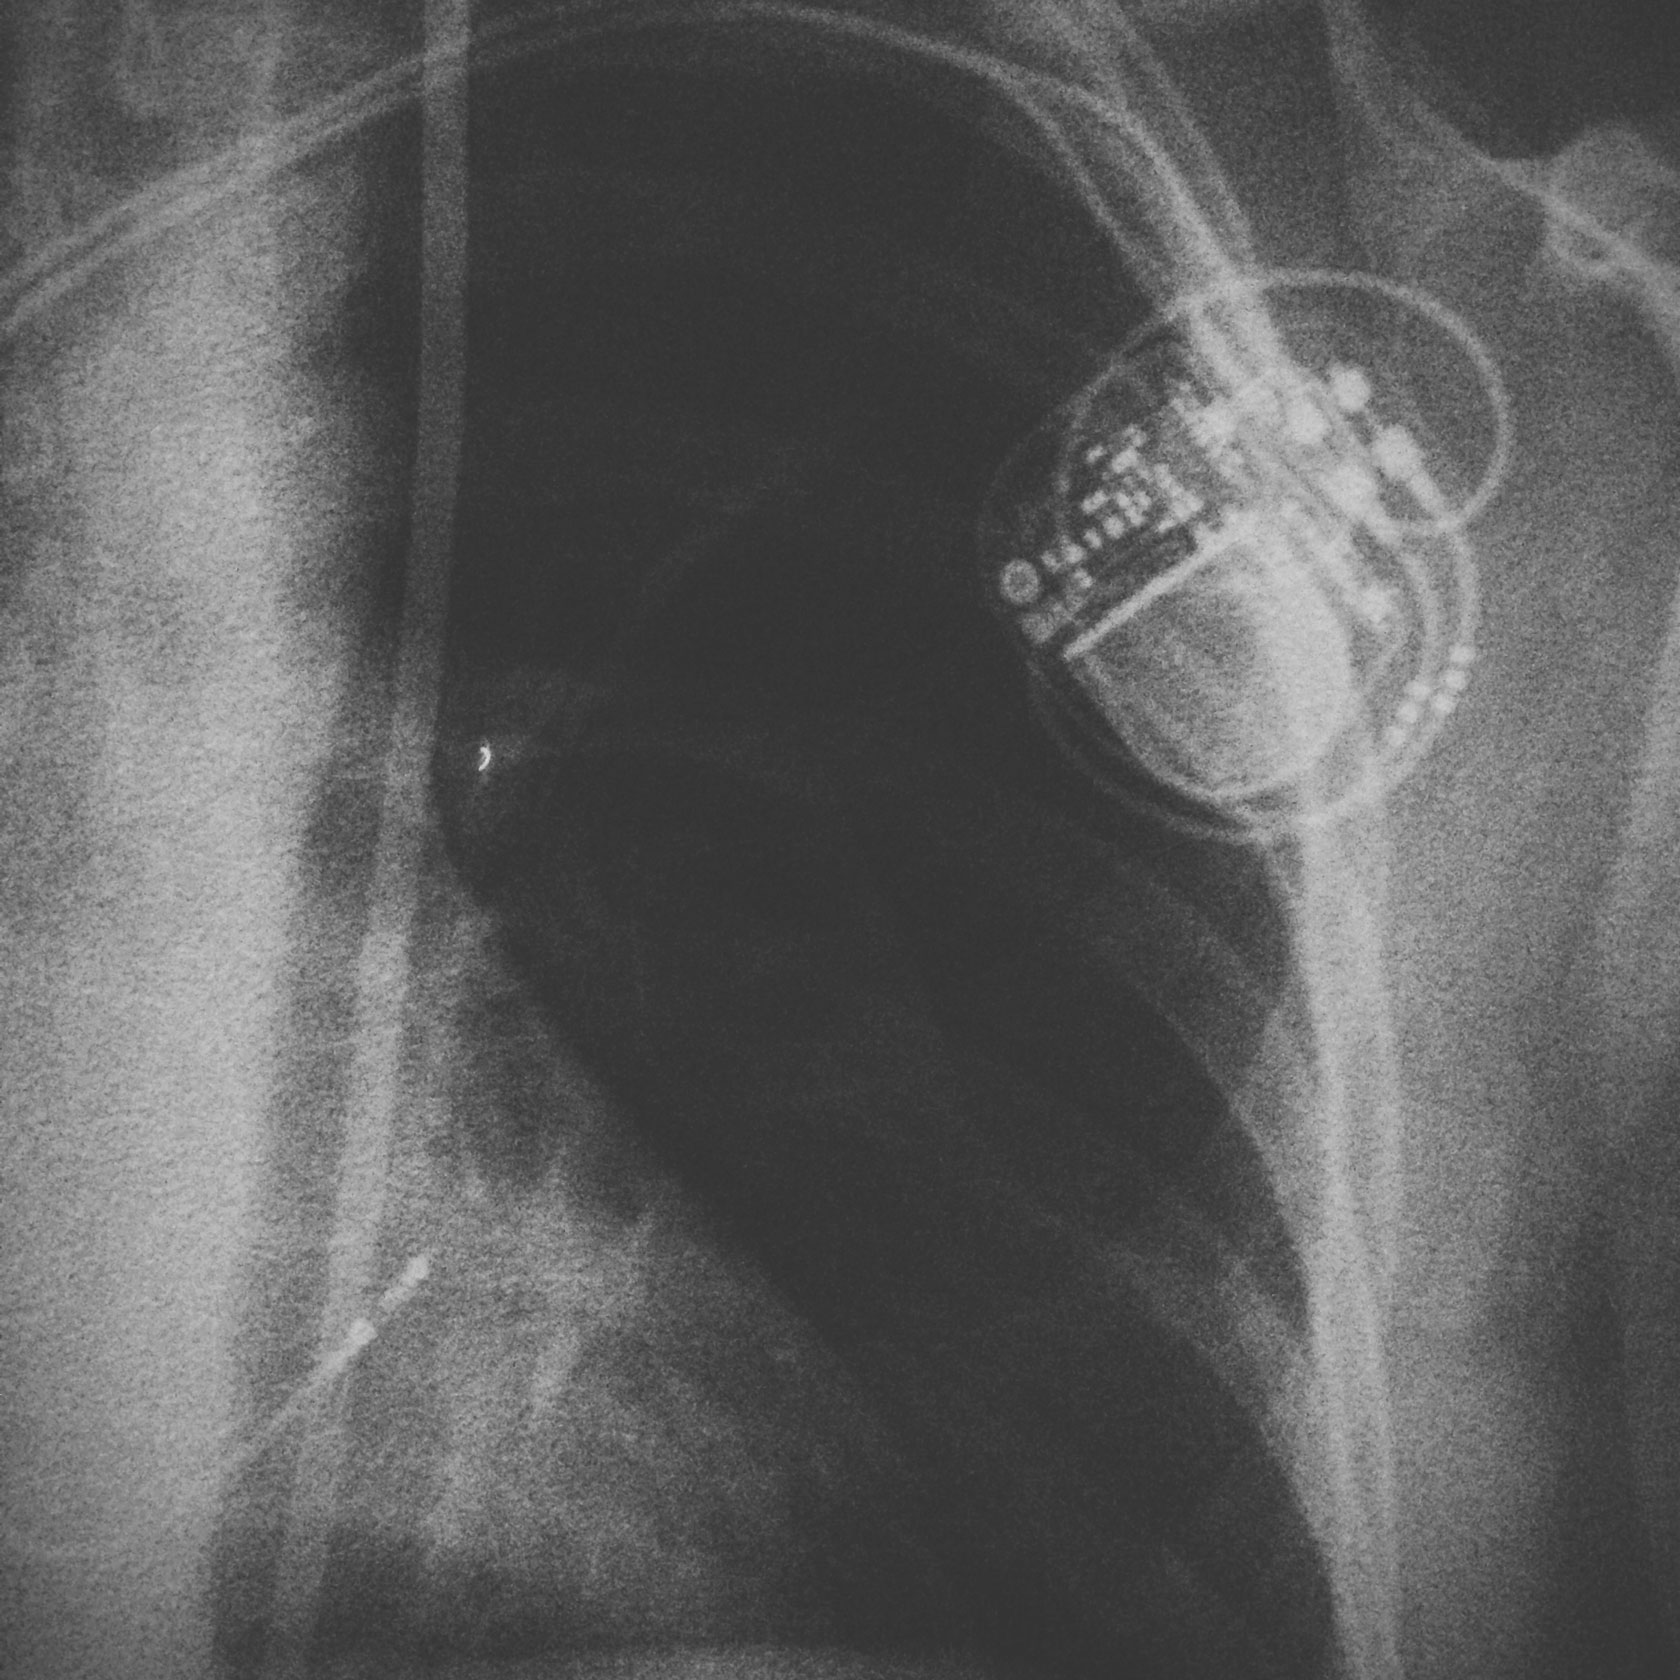

My absence this time is because I had this little box and wires put in my chest last Thursday afternoon. It’s a pacemaker.

The decision was made that I would have a small device implanted into my chest that would constantly monitor my heart. I needed to blackout again. Awesome. Three weeks passed, and in the middle of a doctrine lecture, at exactly 11:31 am, something happened. My heart stopped. Completely. For 5 seconds. We didn’t find this out till a few weeks later, but the problem was worse then we originally thought.

My cardiologist looked at Kirsty and I and said, “Right, we need to get a pacemaker into you as soon as possible”. Plans were then made. Which resulted in last Thursday.